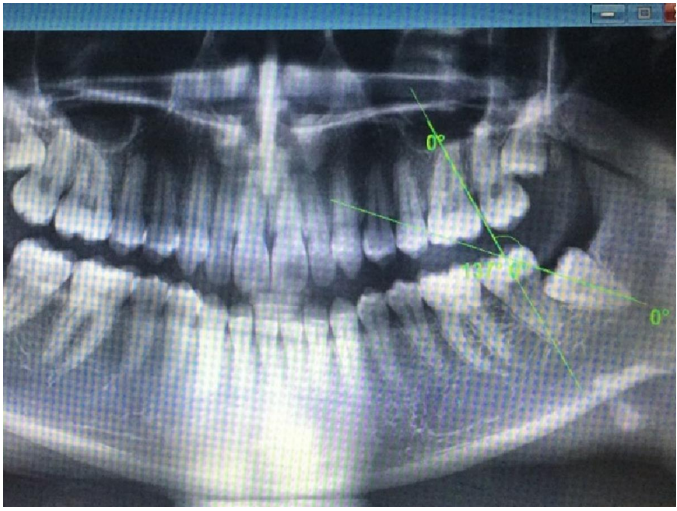

The angulation of the third molar tooth determined by Winter's classification. The angle measured was created by intersection of two vertical lines representing the longitudinal axis of third molar and second molar teeth

The depth of the wisdom tooth in relation to Occlusal plain of the second molar and the coverage of the ascending ramus of the mandible over the third molar tooth was determined by Bell and Gregory's classification The measurements were made using of VIX WIN PRO software version 1 5 a product of Gendex Company

Figll Demonstrating in right side an integrated pattern of classification

(Distoangular impaction according to winter and class 3 position B according to Bell and Gregorys classification)

Impactions seen in fig. 11 are a good example of integrated pattern, reporting the type of impaction with this pattern give good estimation to the operator warn against complications like jaw bone fracture due to mass bone removal in all direction. This will help the operator to have preparedness for such mishaps and, warn the patient and get his consent for such an expected complication